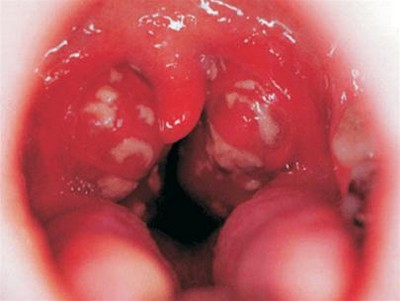

Viêm amidan hốc mủ.